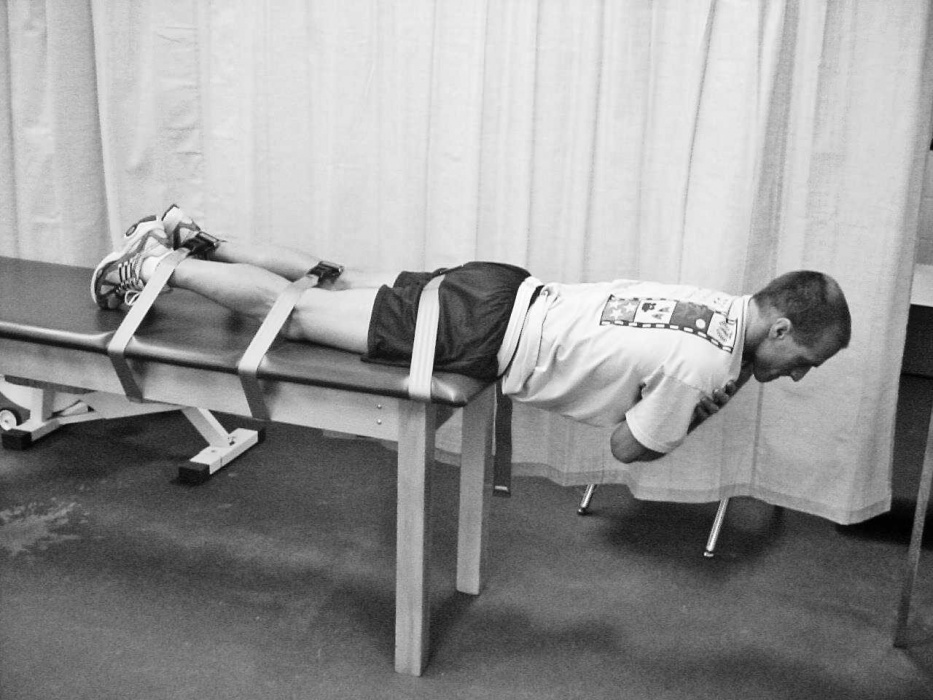

استقامت عضلانی

تناسب اندام همچنین شامل استقامت عضلانی است که توانایی عضله برای ادامه اعمال نیرو بدون خستگی است.

بیماران مبتلا به کمردرد استقامت عضلانی اکستانسور کمری را در مقایسه با افراد غیر مبتلا کاهش داده اند.

استقامت عضلانی شکم در مبتلایان به کمردرد به طور قابل توجهی در مقایسه با افراد در جمعیت سالم کاهش می یابد.

نشان داده شده است که خستگی کمر در نتیجه استقامت عضلانی کم، توانایی فرد را برای احساس موقعیت ستون فقرات کمری کاهش می دهد.

افراد مبتلا به کمردرد مزمن توانایی در کنترل موقعیت ستون فقرات کمری پس از یک کار خسته کننده را مختل می کنند.

این حالت منجر به بی ثباتی کمر می شود.

بیماران مبتلا به کمردرد، درصد بیشتری از فیبرهای گلیکولیتیک نوع I سریع در مقایسه با فیبرهای اکسیداتیو کند دارند.

الیاف تند انقباض به سرعت منقبض می شوند اما به سرعت خسته می شوند و در برابر خستگی مقاومت کمتری دارند.

این باعث می شود این افراد بیشتر مستعد آسیب کمر شوند.

افراد غیر کمردردی دارای درصد بسیار بالاتری از فیبرهای کند انقباض هستند که برای کارهای استقامتی بهترین هستند.

زیرا می توانند وظایف را بدون خستگی انجام دهند و در عضلات مرکزی وجود دارند.